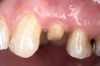

Fig 3. After endodontic treatment, crown lengthening was performed to develop an ideal ferrule effect.

Figure 3

Fig 4. An adequate collar effect of 2 mm of sound tooth structure would provide an anti-rotational feature for the stability of the crown.

Figure 4

Fig 5. Buccal view of optimal ferrule effect with a healthy biological framework.

Figure 5